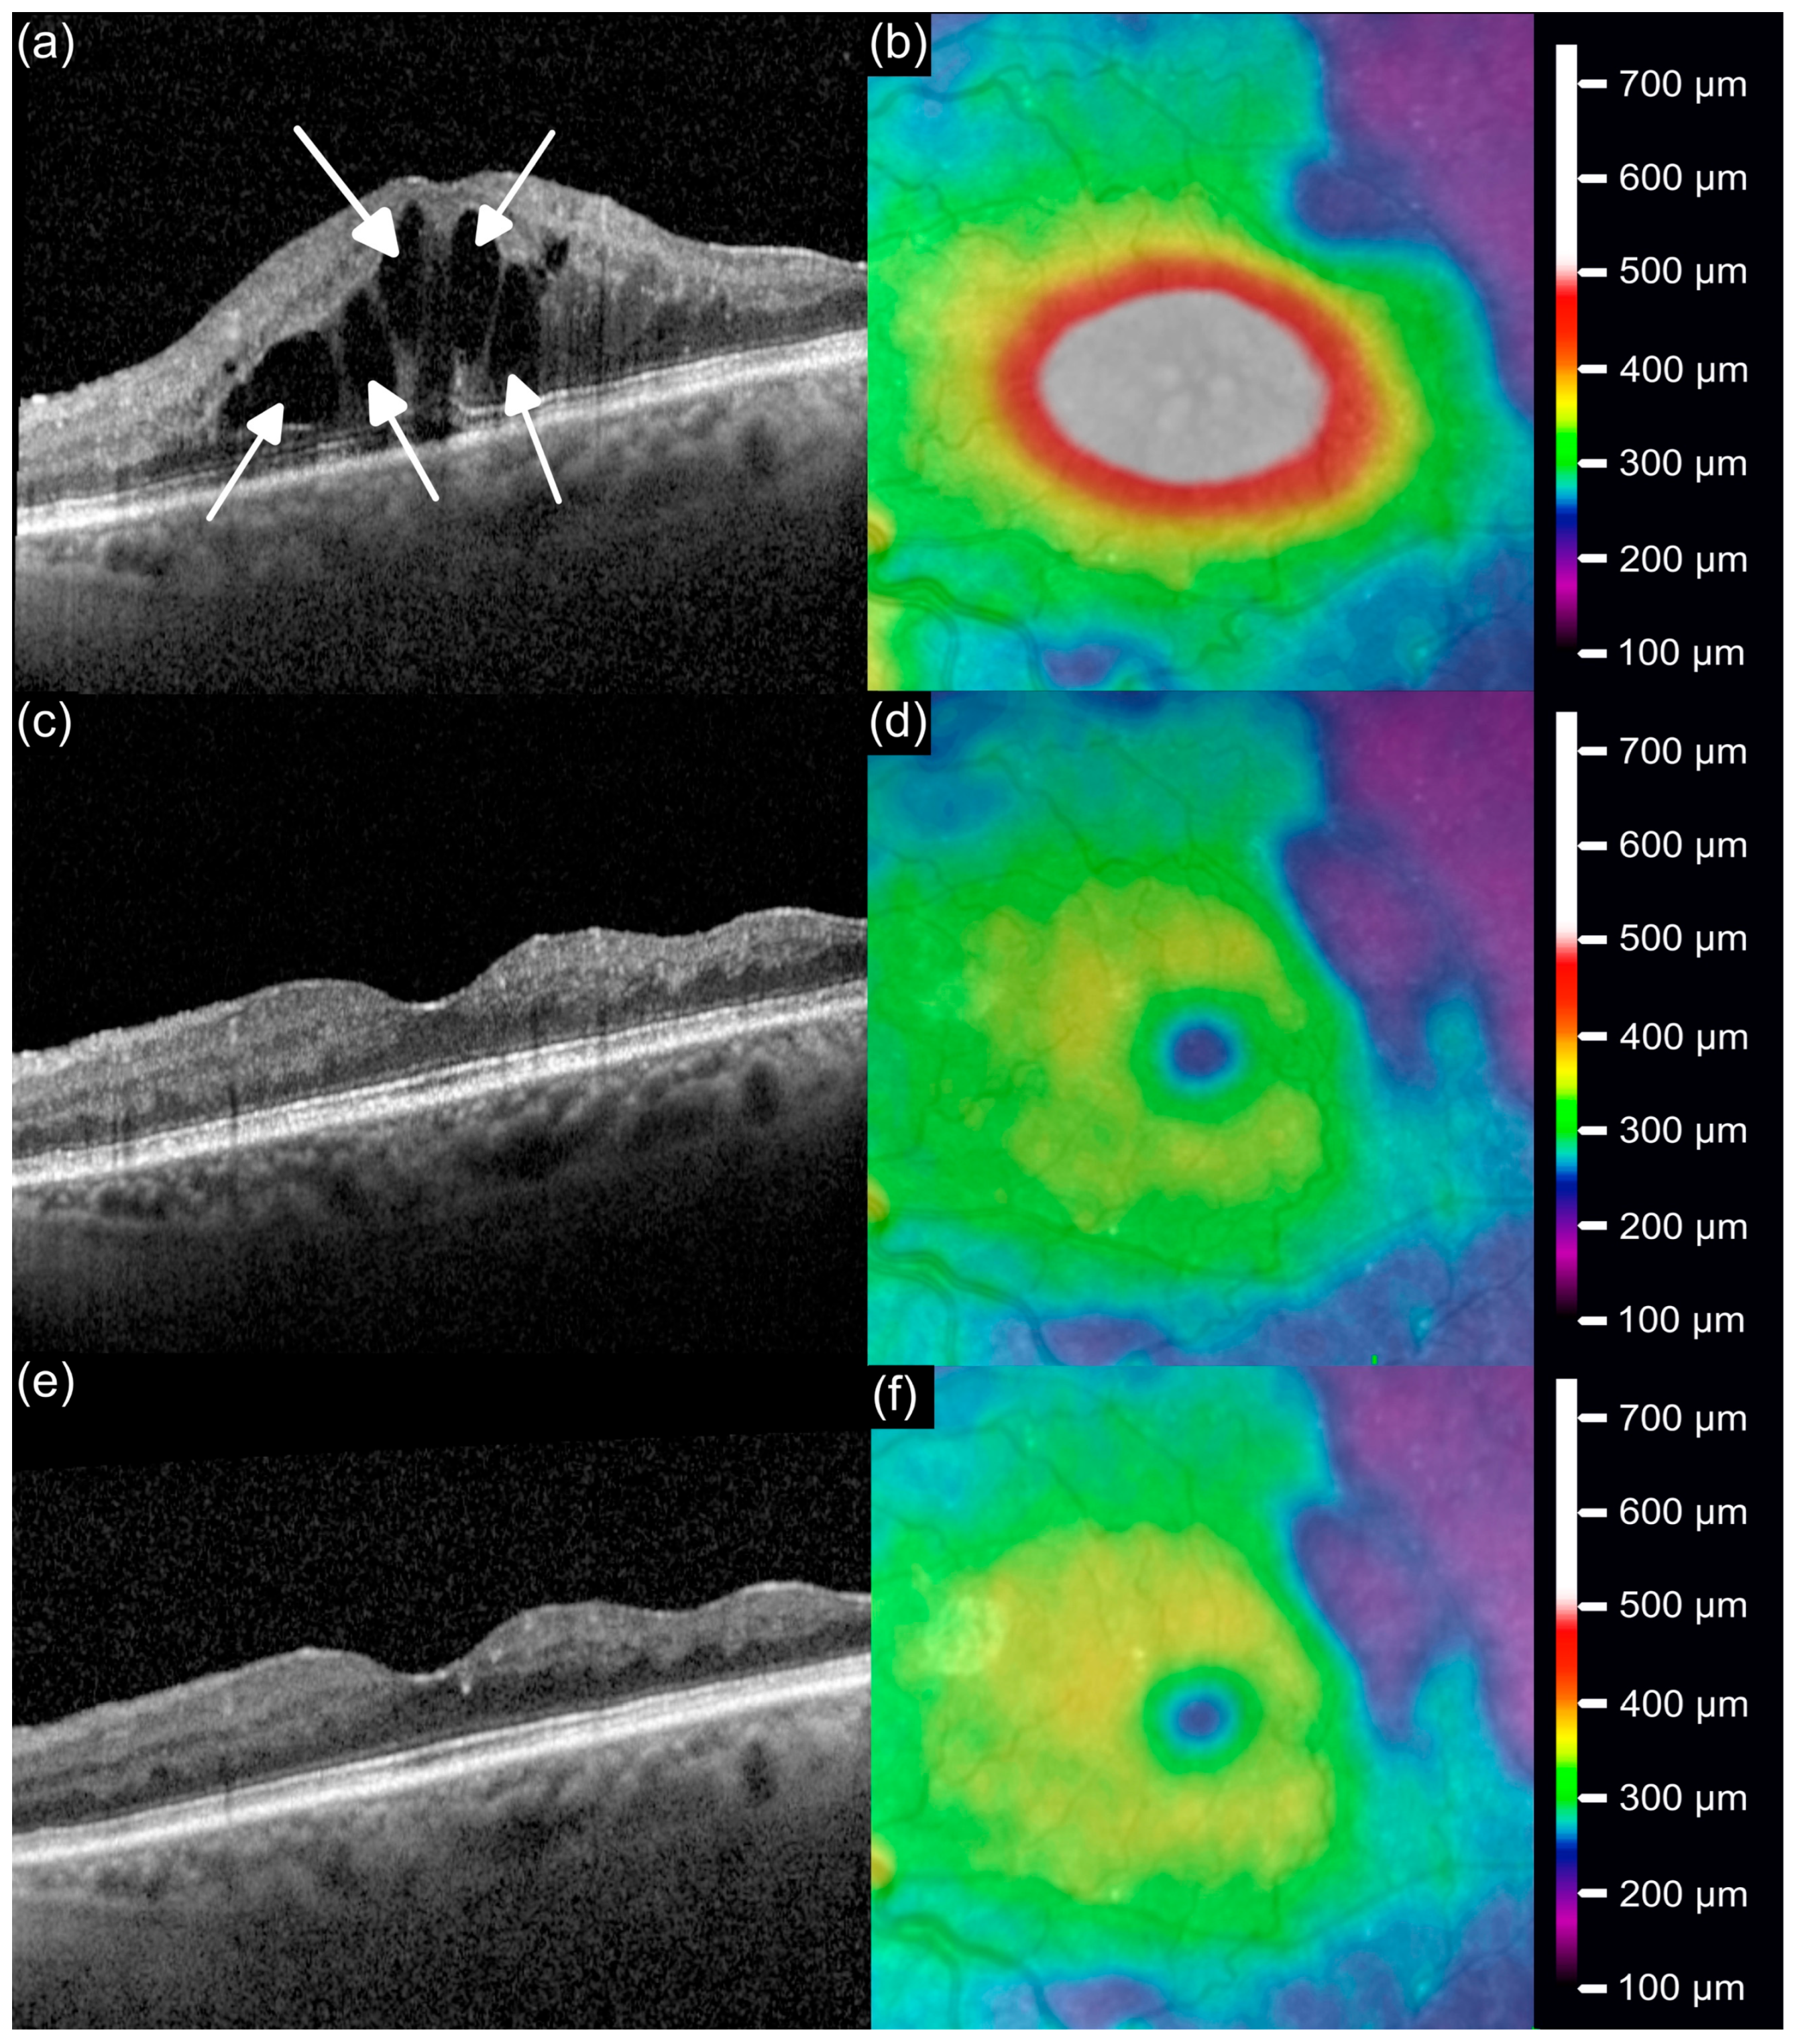

3.3. OCT Anatomical Outcomes